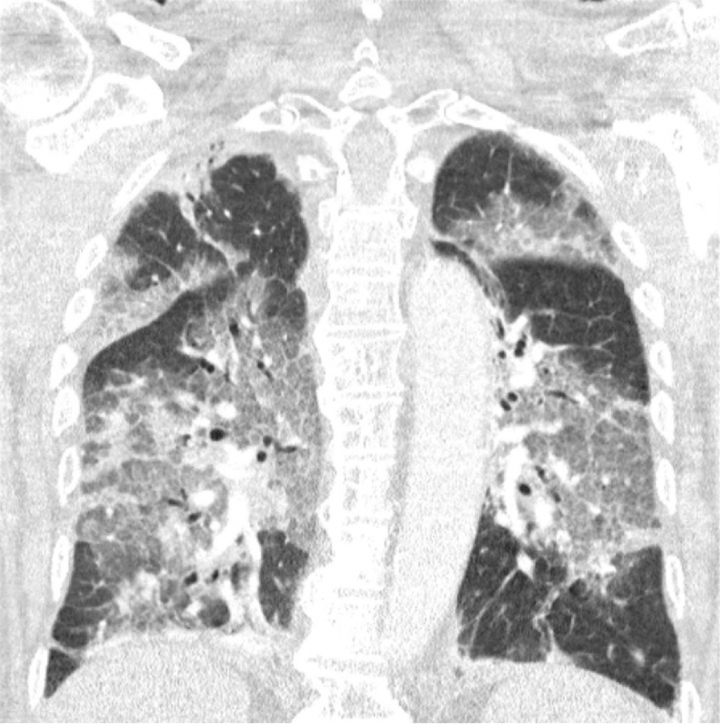

Imagen de los pulmones contagiados con coronavirus del hombre que rechazó la vacuna de AstraZeneca.EFE

“Hoy ingresó en nuestro hospital el primer paciente que se había negado a recibir la vacuna de AstraZeneca tras toda la conmoción en la prensa. Oímos el tremendo pesar en su voz y la desesperación en sus ojos. El virus lo ha atacado y podría haberse evitado. Con su permiso, compartimos su escáner de pulmón. No es necesario ser un especialista en pulmones para reconocer la devastación, ni epidemiólogo para explicar los riesgos de no estar vacunado”, alertaron.